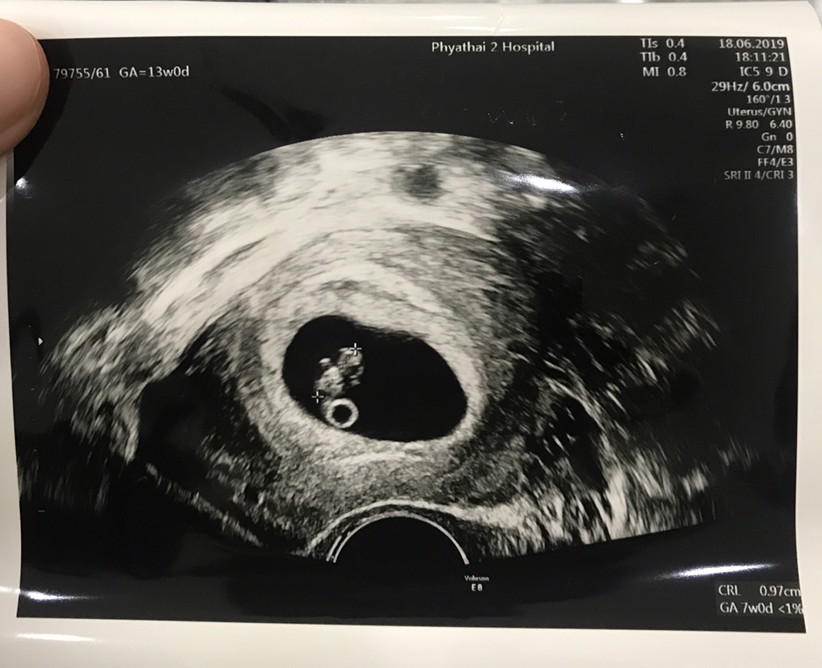

อายุครรภ์ 7 สัปดาห์

7 สัปดาห์ค่ะ ซาวด์ผ่านช่องคลอด

เห็นค่ะ แต่จะตัวเล็กมากๆๆค่ะ